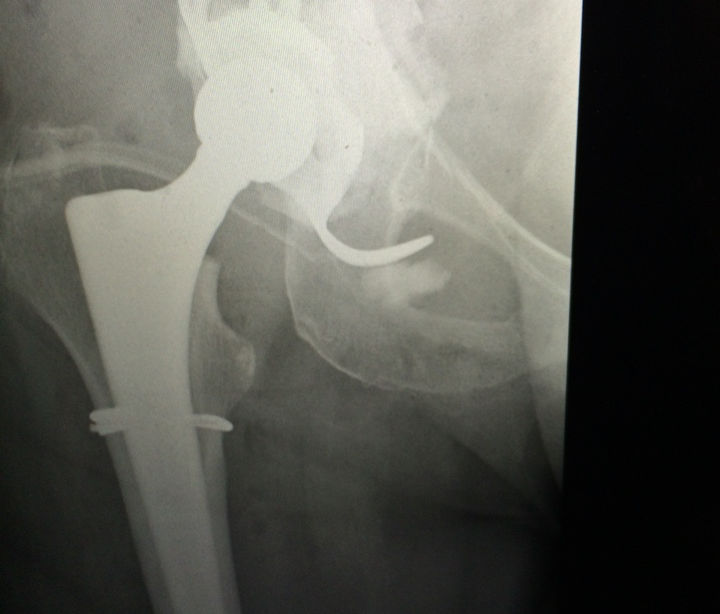

Frattura con sfondamento del bacino e della protesi - Ricostruzione del bacino con innesto osseo da cadavere